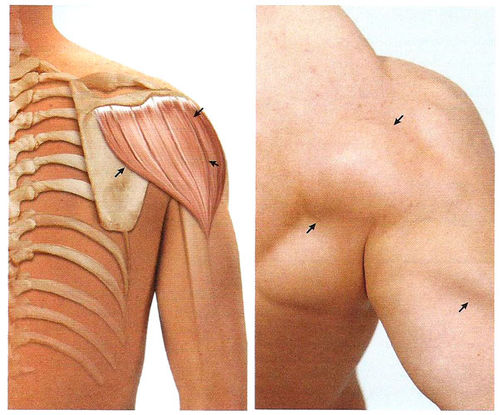

Фотографии поддельтовидной мышцы плечевого сустава